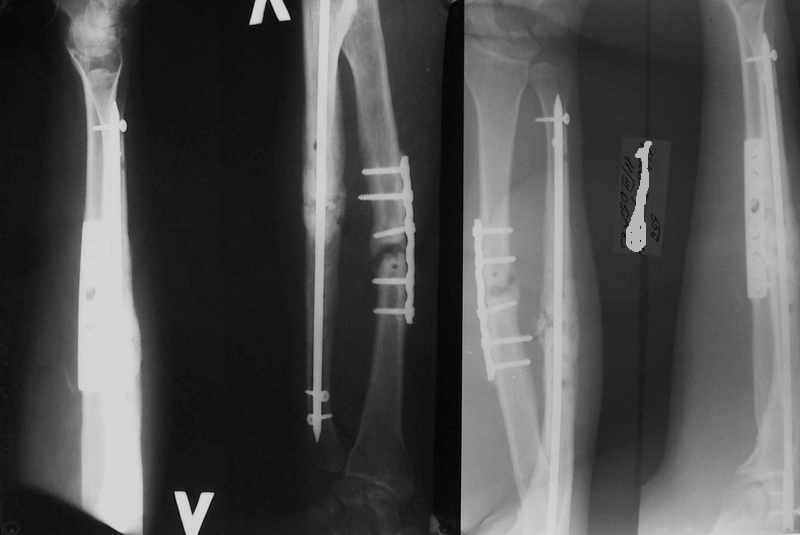

Уважаемые коллеги!Доводим до Вашего сведения наш скромный опыт применения блокирующего остеосинтеза локтевой кости (4случая), четверо пациентов с ложными суставами локтевой кости. Во всех случаях оперировали открыто с костной аутопластикой.Технических проблем введения штифтов не было. В одном случае отвалилась резьбовая часть спицы при прокс. блоке (оставлена как блокирующий винт). Дистальное блокирование осуществляли используя вместо кондуктора сп. Киршнера изгибая ее конец о край кондуктора на необходимую длину до отверстий. Наши первые впечатления классные. Очень быстрая функциональная реабилитация без гипса и консолидация через 2 мц. На представленных фотографиях двое пациентов.Тот, у которого якобы не срастается лучевая кость на АО пластине, уже катался на горн. лыжах, а сейчас опять уехал на Эльбрус -экстремал ,,,нов. С уважением Нагога Александр, ортопедическая клиника ОРТО, Самара.

А зачем же неправильный гвоздь использовать, который нарушает? Наоборот, с помощью гводя нарушенная форма костей очень даже эффективно восстанавливается (см. пример). А неправильный

остеосинтез можно сделать чем угодно.